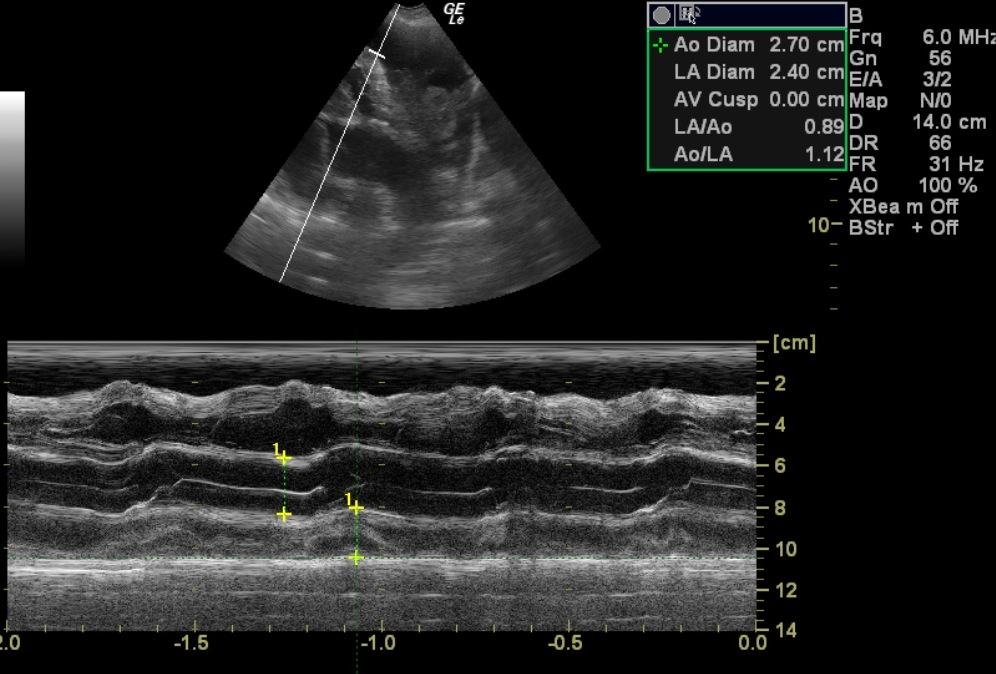

A 10-year-old SF Rottweiler cross was presented with a history of lethargy and not doing right. On physical examination depression and polypnea was evident. Abnormalities on serum biochemistry were elevated liver enzyme activity. Cardiomegaly was present on survey radiographs. Blood pressure was normal (140).